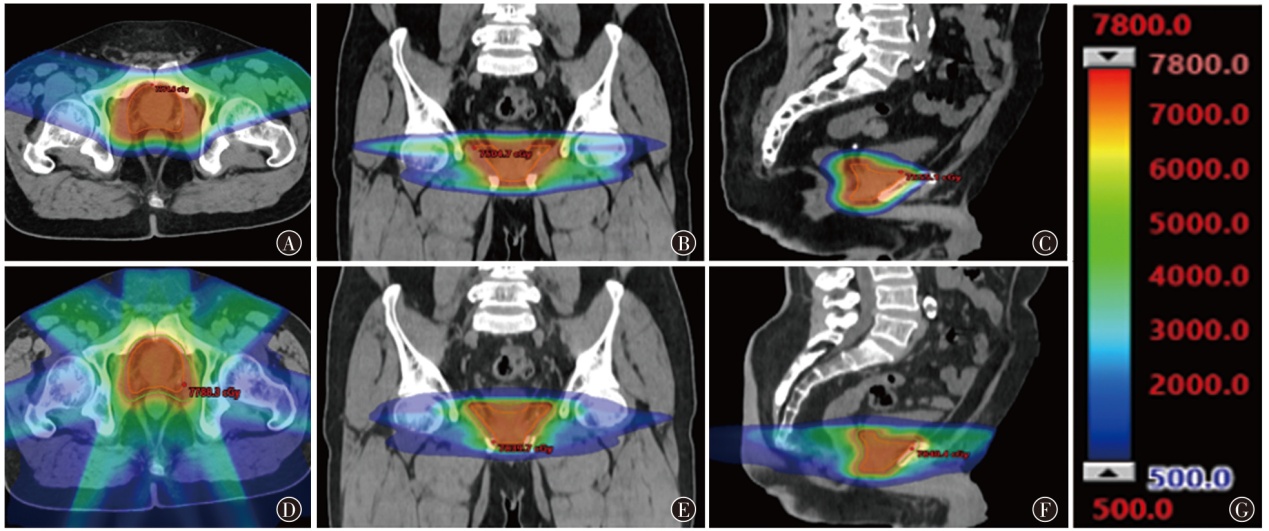

目的探讨质子调强放疗(IMPT)和光子固定野调强放疗(IMRT)应用于典型腹盆部肿瘤的剂量学特点。方法以2024年1月至6月山东省肿瘤防治研究院(山东省肿瘤医院)收治的3例腹盆部肿瘤(肝癌、宫颈癌和前列腺癌各1例)患者为研究对象,根据临床靶区和危及器官限值的要求,分别设计IMPT和IMRT两种放疗计划。评估3例患者两种放疗计划的靶区适形指数(CI)、均匀性指数(HI)和梯度指数(GI)及危及器官剂量学参数,通过评估体内10%、30%和50%处方剂量区域的体积比较患者体内额外的剂量沉积。结果3例患者IMPT计划的CI值(分别为0.61、0.62和0.43)、HI值(分别为0.053、0.075和0.020)、GI值(分别为3.45、2.63和3.80)均小于IMRT计划(CI分别为0.82、0.81和0.86;HI分别为0.060、0.120和0.080;GI分别为7.28、4.76和4.66)。与IMRT计划相比,在肝癌患者中,IMPT计划可使正常肝组织和右肾的Dmean及脊髓的Dmax分别降低37.8%、78.5%和13.2%;在宫颈癌患者中,IMPT计划可使小肠的V30,膀胱、直肠、骨髓的Dmean和脊髓的Dmax分别降低22.0%、15.7%、14.3%、12.6%和4.8%;在前列腺癌患者中,IMPT计划可使膀胱和直肠的Dmean分别降低14.9%和36.5%,但IMPT计划使左侧股骨头的Dmean及V40分别升高了35.3%和6.1%,使右侧股骨头的Dmean及V40分别升高了23.6%和10.8%。3例患者体内10%、30%和50%的处方剂量区域所占的体积,IMPT计划比IMRT计划减少了48.9%~64.8%、22.0%~47.0%、22.0%~57.7%。结论腹盆部肿瘤的IMPT和IMRT计划比较,IMPT计划在降低正常肝脏、肾脏、脊髓、小肠、直肠和膀胱等器官的剂量方面有优势;对于股骨头的剂量,IMPT计划优势并不明显;IMPT计划可显著减少患者体内额外的剂量沉积。

ObjectiveTo explore the dosimetric characteristics of intensity modulated proton therapy (IMPT) and intensity modulated radiation therapy (IMRT) for typical abdominal and pelvic tumors.MethodsThree patients with abdominal and pelvic tumors (one case each of liver cancer,cervical cancer,and prostate cancer) admitted to Shandong Cancer Hospital and Institute from January to June 2024 were selected as the research subjects. IMPT and IMRT plans were designed for each case based on clinical target volume (CTV) and organs at risk (OARs) constraints. Dosimetric parameters,including conformity index (CI),homogeneity index (HI),and gradient index (GI) for target coverage,as well as OARs dose metrics,were evaluated. The volume of additional dose deposition in the body was compared by assessing regions receiving 10%,30%,and 50% of the prescription dose.ResultsFor all three cases,IMRT plan demonstrated higher CI values (0.82,0.81,and 0.86) compared to IMPT plan (0.61,0.62,and 0.43). IMPT plan yielded lower HI values (0.053,0.075,and 0.020) than IMRT plan (0.060,0.120,and 0.080) and lower GI values (3.45,2.63,and 3.80vs. 7.28,4.76,and 4.66 for IMRT plan). In liver cancer,IMPT plan reduced the Dmeanof normal liver tissues and right kidney by 37.8% and 78.5%,respectively,and decreased the Dmaxof spinal cord by 13.2%. For cervical cancer,IMPT plan reduced the V30of the small bowel by 22.0%,Dmeanof the bladder,rectum and bone marrow by 15.7%,14.3% and 12.6%,and spinal cord Dmaxby 4.8%. In prostate cancer,IMPT plan lowered bladder and rectal Dmeanby 14.9% and 36.5%,respectively,but resulted in an increase of 35.3% and 6.1% in the Dmeanand V40of the left femoral head,respectively,and an increase of 23.6% and 10.8% in the Dmeanand V40of the right femoral head,respectively. IMPT plan reduced the volumes receiving 10%,30%,and 50% of the prescription dose by 48.9%-64.8%,22.0%-47.0%,and 22.0%-57.7%,respectively,compared to IMRT plan.ConclusionsComparison between IMPT and IMRT plans for abdominopelvic tumors: IMPT plan offers advantages in reducing doses to normal organs such as the liver,kidneys,spinal cord,small intestine,rectum,and bladder. However,its advantage is less pronounced regarding the dose to the femoral heads. IMPT plan notably minimizes additional dose deposition within the body.